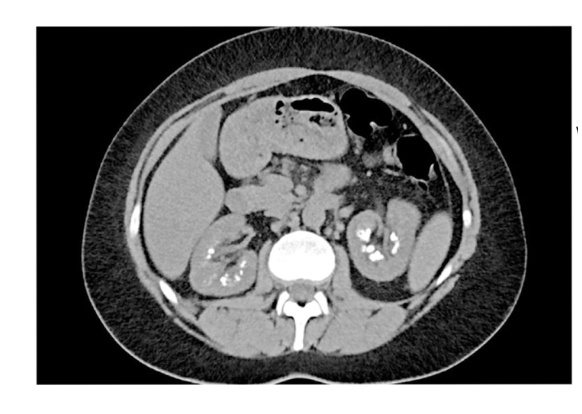

What is the CT + Pathology?

Abdomen CT C+

- In arterial phase as the abdominal

aorta has maximum opacification • Path = renal cell carcinoma

- Heterogenous mass on the kidney

with poorly defined margins